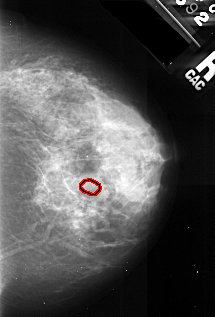

A_1029_1.RIGHT_CC

RIGHT_CC LINES 4426 PIXELS_PER_LINE 3001 BITS_PER_PIXEL 16 RESOLUTION 42 OVERLAY

FILE: A_1029_1.RIGHT_CC.OVERLAY

TOTAL_ABNORMALITIES 1

ABNORMALITY 1

LESION_TYPE CALCIFICATION TYPE PLEOMORPHIC DISTRIBUTION CLUSTERED

ASSESSMENT 4

SUBTLETY 3

PATHOLOGY MALIGNANT

TOTAL_OUTLINES 1

BOUNDARY